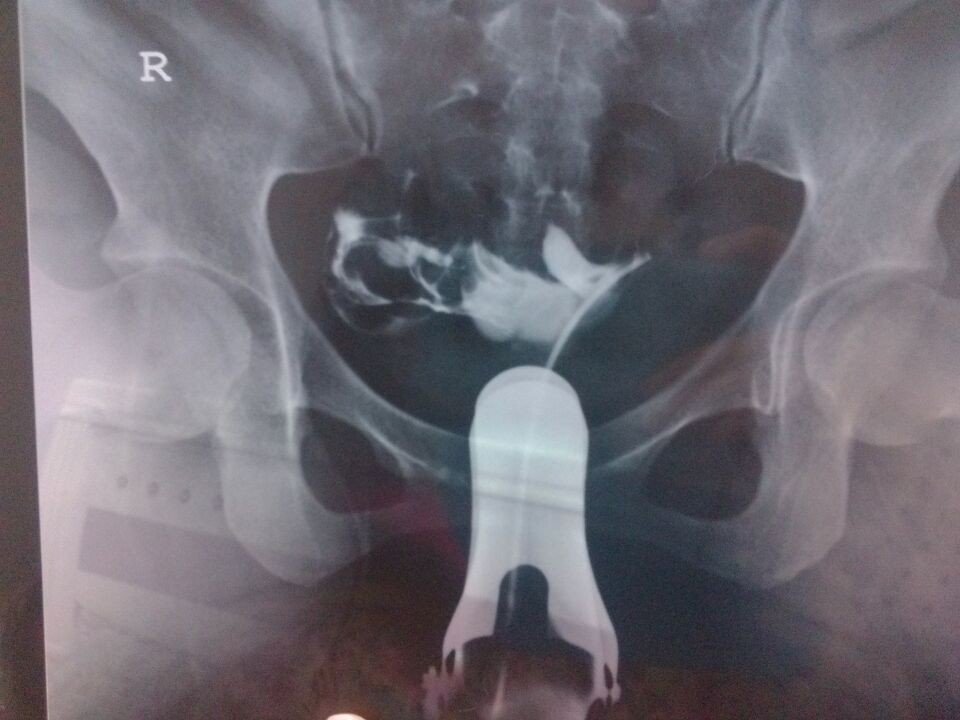

左侧输卵管各段未见对比剂弥散征象,10分钟后摄片,盆腔内见多量泛影葡胺弥散,呈团片状影,未见明显输 卵管淤积影, 诊断提示:1、右侧输卵管尚通畅2、左侧输卵管未显影,建议结合临床考虑3、慢性盆腔炎可能有19mm盆腔积液想请问一下医生,这个是不是左侧输卵管堵塞?要不要做手术?疏通左侧输卵管,谢谢 点击展开 匿名用户 2014-03-02 18:46 为您推荐: 其他回答 病情分析: 从你的检查结果来看是左输卵管堵塞的表现 指导意见: 从你现在的情况来看考虑是慢行盆腔炎症造成的输卵管堵塞,建议你考虑腹腔镜手术治疗 韩正思_SjH7 2014-03-02 19:04 相关问题 造影剂在盆腔呈片状、斑片状、索条状及结节状弥散,造影剂弥散欠佳,双侧输卵管疑有造影剂滞留 结婚多年一直不孕,去做了造影输卵管是通畅的,造影剂盆腔弥散不佳,医生让我回来等半年,半年过去了,这 子宫形态正常,输卵管左右通 造影剂进入盆腔 24小时弥散片示,弥散差,造影剂部分团